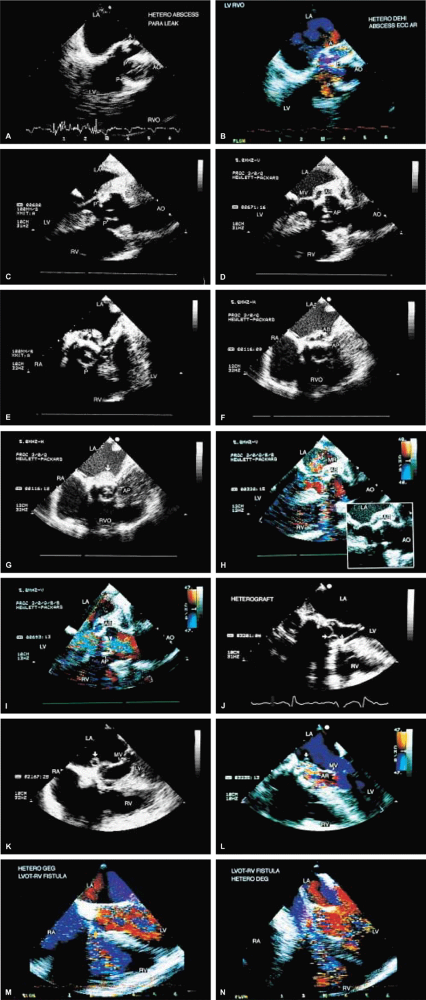

FIGURE 5.2. St. Jude mitral prosthesis: thrombus. A–F. Localized echo densities consistent with thrombus (T) are noted on the St. Jude prosthesis (P) in two different patients (A,B and C–F). In both patients, thrombus prevented the opening of one of the leaflets of the prosthesis. F. Continuous wave Doppler shows a flat velocity profile in early diastole (arrows) and a high peak velocity of 152 cm/sec consistent with obstruction. G and H (one patient) and I (another patient) show two other patients with thrombosed (TH, T) St. Jude mitral prostheses. The echo densities representing thrombus are seen on the atrial side of the prosthesis. Thrombi are less dense than the metallic components of the prosthesis and are different from prosthetic reverberations, which are anteriorly directed, more prominent, and have larger linear echoes. In addition, reverberations are not seen on the atrial aspect of the prosthesis. AO, aorta; LA, left atrium; LV, left ventricle; MP, mitral prosthesis; RA, right atrium; RV, right ventricle; RVO, right ventricular outflow tract. |

FIGURE 5.3. St. Jude mitral prosthesis: paravalvular regurgitation. A. A large eccentric jet (arrowheads) coursing medially along the atrial septum is seen originating beyond the edges of the prosthetic elements (P). B. The paraprosthetic leak (arrowheads) is located laterally. There is also a large zone of flow acceleration (FA), which is clearly located outside the confines of the prosthetic valve (P). C. The dehisced area (arrow) is clearly seen, and a wide jet of paravalvular regurgitation (oblique arrow) can be seen coursing through it (D). The vertical arrows point to two small jets of normal valvular regurgitation through the St. Jude prosthesis. E,F. Another patient with dehiscence of sutures and pansystolic paravalvular regurgitation. G,H. Another patient with suture dehiscence (arrow in G) and severe eccentric MR (arrowheads), with a large FA on the ventricular aspect of the St. Jude prosthesis. I. There is eccentric periprosthetic MR (white arrows) as well as eccentric TR (yellow arrows) moving along the atrial septum. Two small normal jets of MR also are seen originating from the St. Jude prosthesis. LA, left atrium; LV, left ventricle; MP, mitral prosthesis; RA, right atrium; RV, right ventricle;RVO, right ventricular outflow tract. |

FIGURE 5.4. A,B. St. Jude mitral prosthesis: ectopic position. In this patient, the St. Jude prosthesis (P) is attached to the wall of the left atrium (LA) (upper arrowhead in B) rather than to the valve ring (lower arrowheads). LV, left ventricle; RA, right atrium; RV, right ventricle. |